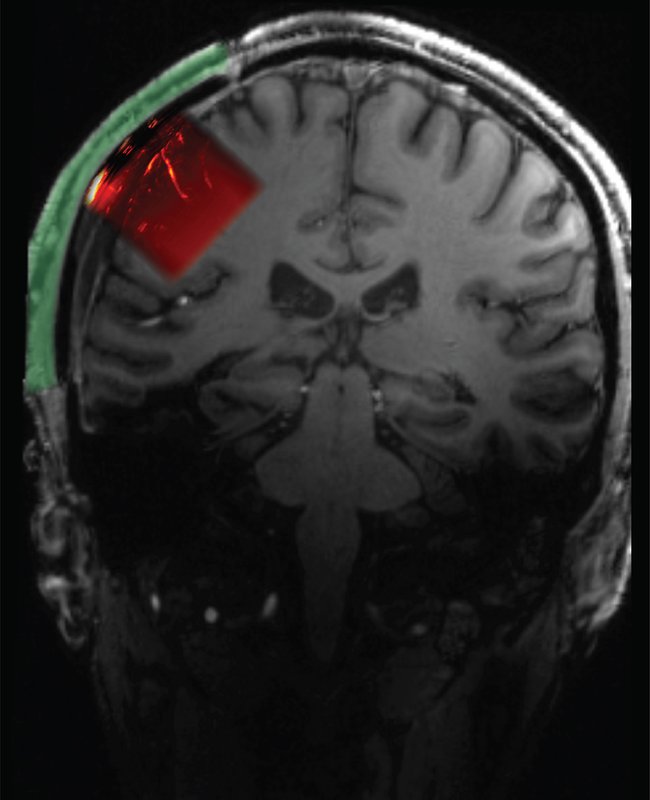

Claire Rabut, formerly a postdoc in Shapiro's lab and currently a visitor in chemical engineering at Caltech, experimented with materials used for cranial implants and found that polymethyl acrylate, already favored for its sterility and strength, was also transparent to the acoustic signals relied upon by ultrasound. Sumner Norman, also a former postdoc in Andersen's and Shapiro's labs, worked with Rabut to create an implant that, according to Norman, "would serve not only as a safe and cosmetically transparent prosthetic, but also be transparent enough that ultrasound waves could achieve the high sensitivity needed for functional brain imaging."

The resulting implant was 4 millimeters thick overall but had a 2 millimeter-thick window through which an ultrasound transducer could image a brain region known as the posterior parietal cortex and, behind it, the motor cortex. "This area of the brain, which is important for forming intentions and carrying out motor actions, has already been thoroughly studied via other methods in our lab," Andersen says. "With ultrasound, we can image the brain up to a resolution of one-fifth of a millimeter."